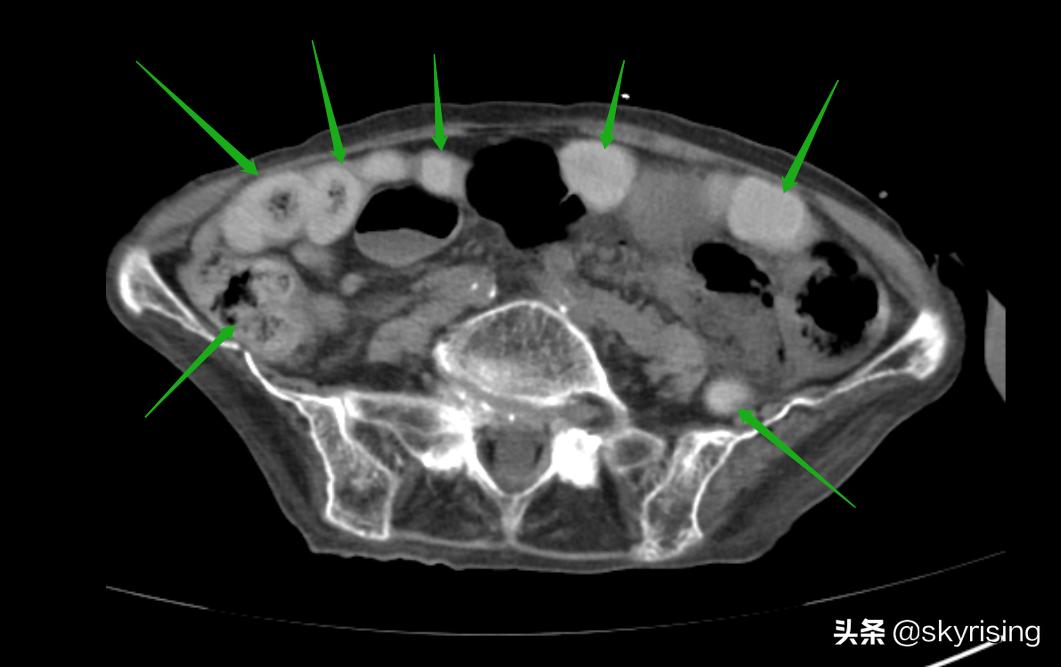

下图绿色箭头所示为主要为横结肠肠管,管壁增厚,密度增高,肠管未见扩张、积气、积液。考虑出血可能。那么还需要考虑的是动脉还是静脉原因引起的出血,如果是动脉栓塞,供血不足肠管管壁增厚、密度减低,中心见层状水肿密度影。静脉栓塞可以是出血性表现,密度增高,血肿外溢等。

下图黄色箭头所示小肠回肠肠襻呈U型改变,肠管扩张,肠壁增厚,肠壁间见垂直线性气体密度影。这是典型肠系膜血管栓塞的典型表现,可能是动脉也可能是静脉,需要结合增强检查。